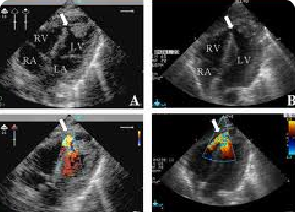

ECHOCARDIOGRAPHY

Echocardiogram, or simply echo, is a sonogram of the heart. Echocardiography uses standard two-dimensional, three-dimensional